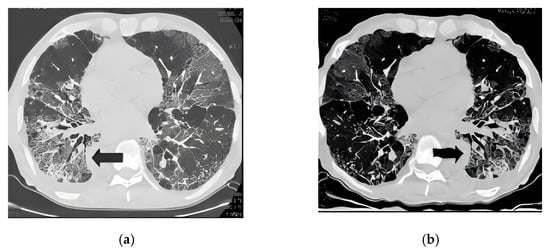

2.2. Image Preprocessing